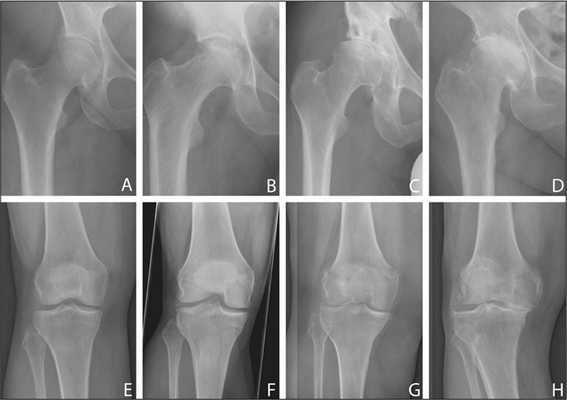

Деформирующий остеоартроз — одно из ведущих заболеваний опорно-двигательного аппарата. Он проявляется дегенеративно-дистрофическими изменениями суставных поверхностей. Частота встречаемости составляет от 3 до 12% среди взрослого населения. В этом показателе на первом месте стоит поражение тазобедренного сустава, а на втором – коленного.

- деформирующий артроз II-III степени, с преимущественным поражением одного сегмента коленного сустава;

- при изолированном асептическом некрозе мыщелка бедренной или большеберцовой кости голени;

- аутоиммунные заболевания, при которых наблюдаются ДДИ суставных тканей – болезнь Бехтерева, СКР (системная красная волчанка), подагра, ревматоидный артрит;

- неудачно сросшийся перелом.

Динамика болезни на рентгене.

Согласно диагнозу, возрастным и весовым критериям, физическим данным и сопутствующим заболеваниям, специалист выбирает наиболее эффективную тактику имплантации:

- – протезированию подлежит только одна из полукруглых возвышенностей бедренной кости с подлежащим к ней проксимальным фрагментом большеберцовой кости (применяется у пожилых пациентов и у лиц с низкой физической активностью);